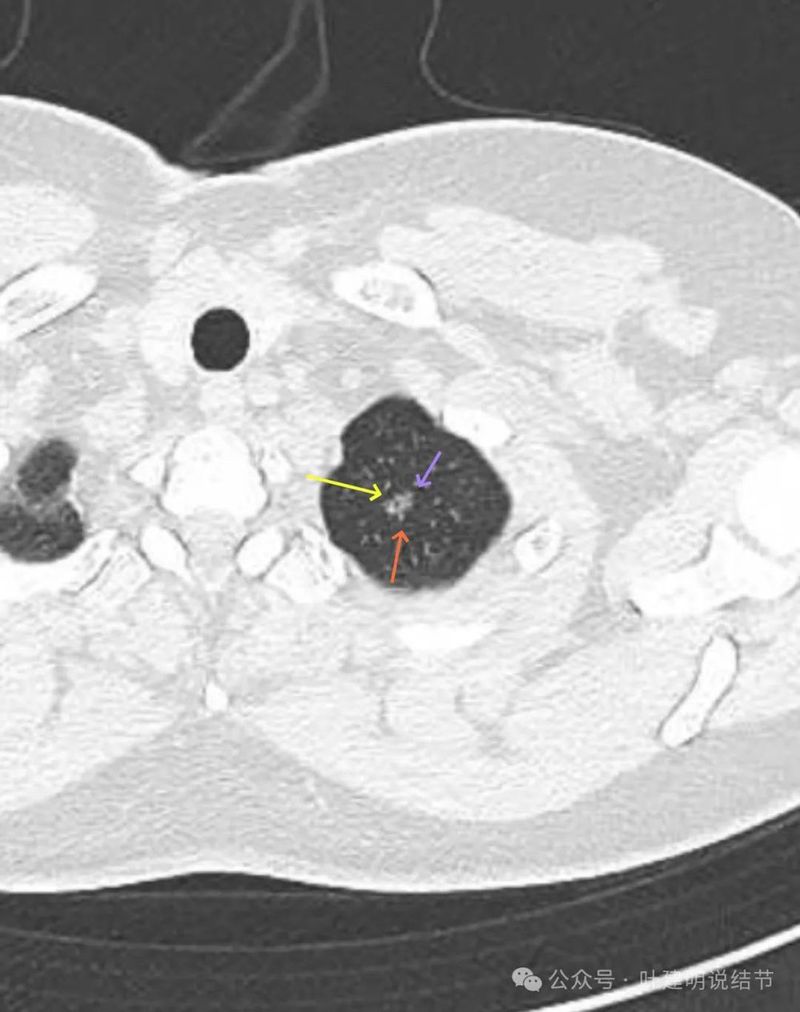

灶内细支气管扩张,边缘有小血管进入,表面不平有小棘突或毛刺,灶内密度不均,有点状高密度。